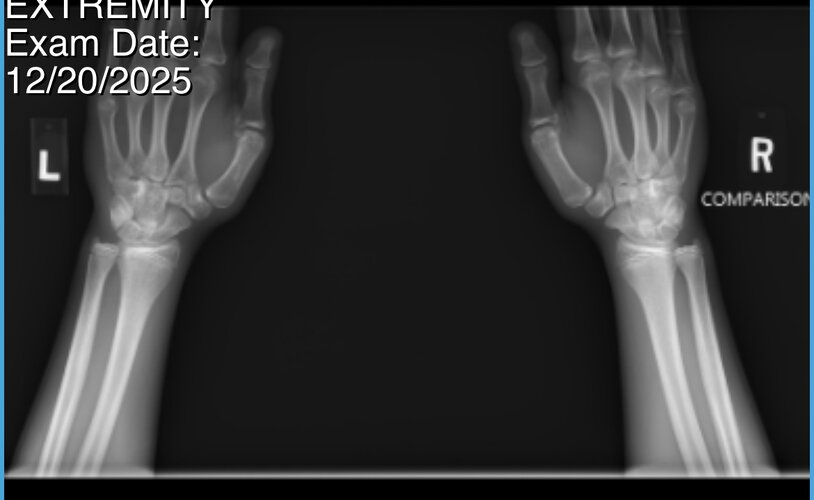

i’m 15 1/2, my plates are beginning to close, and i don’t want to be stuck in this fucking body forever, i’d do anything for aromasin or gh rn, is it truly over for me, if i stick to the gym ill just be a short stubby guy who no woman would want to approach. then again i could find a woman who truly loves me regardless of my height, but thats highly unlikely.:feelswhy: